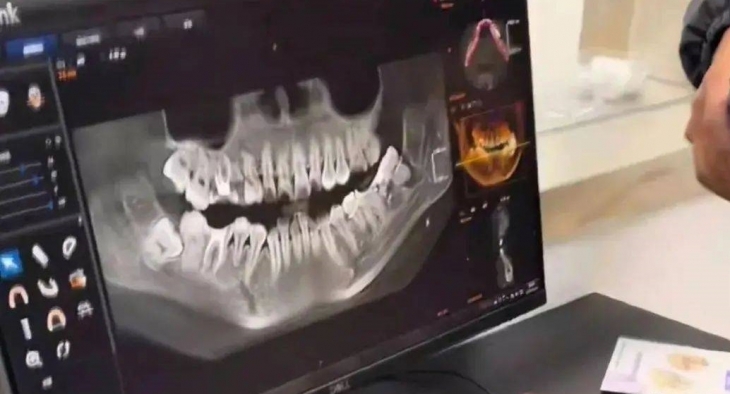

사랑니를 발치하러 병원에 갔던 한 중국 여성이 다른 치아를 수술 받고 의료 과실을 주장하다가 숨졌다. SNS 캡처